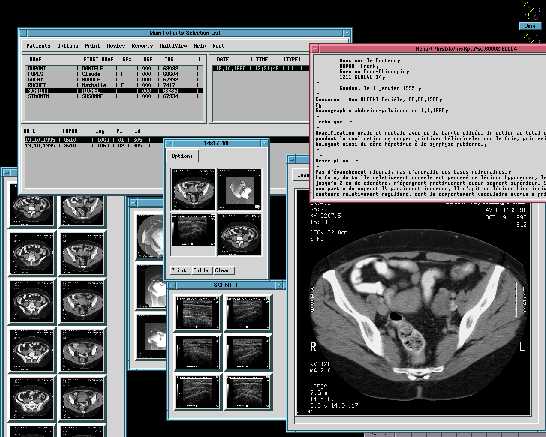

Esto es lo que dije a un amigo suizo que me llamo aqui en España, este explotaba Solaris, X11R4 y Motif 1.1 para los PC's, cada licencia le costaba la bagatela de 8.000 dolares y estaba buscando algo "mas barato", le comente el coste de Linux, no me colgo el telefono porque me tiene aprecio, pero si que me dijo algo que sonaba a "borracho", el caso es que lo compro. Este buen hombre posee una empressa (DAPSYS. SA ) dedicada a la informatica hospitalaria, su especilidad es el archivado de imagenes radiologicas y su restitucion en pantalla, sea con X11 y Motif o Win95.

Esta empresa tenia unas pocas instalaciones ya realizadas en Suiza, cuando de Canada se les presento un dia (casi sin avisar) dos vendedores de una muy importante empresa americana, estos no venian a vender sino comprobar "algo" que "alguien" les habia comentado en el RSNA de Chicago, el RSNA es el evento mundial en el tema de la radiologia. Dos meses despues el director de Dapsys se fue hacia Montreal con su "portatil" para enseñar el producto a unos cuantos doctores, tres meses despues (y 504 años despues de Colon) llego yo a las Americas para hacer la primera instalacion en aquel continente de Iris. Iris es la aplicacion de archivado y restitucion de imagenes radiologicas.

Ademas Iris permite centralizar por paciente TODOS los eventos radiologicos, cada imagen tiene grabada en ella el nombre, apellidos y codigo de paciente, Iris es capaz, mediante tratamiento OCR, extaer esos datos de la imagen y archivar la o las imagenes del paciente junto a las existentes (de haberlas).

Para un paciente determinado se pueden presentar X exploraciones de varias modalidades. Una exploracion es un examen radiologico, un examen puede tener una o X imagenes o disparos. Una modalidad es un aparato capaz de producir imagenes radiologicas sea por Rayos-X, ultrasonidos, resonancia magnetica, etc...

Cuando se producen las imagenes estas llegan directamente al servidor, este tiene que ser capaz de "leer" la imagen y extraer los datos del paciente, para reenviar "rebotar" la imagen a las estaciones de visualizacion y archivar con los datos del paciente leido, para poder devolver la o las imagenes en peticiones posteriores.

Antes de archivar una imagen esta pasa por un proceso de "limpieza" y compresion no destructiva. Conseguimos ratios de 60% en compresiones, podriamos llegar a mas pero seria en detrimento de la eficacia tanto en el archivado como en la posterior restitucion.

Segun las pruebas realizadas una imagen de 512x512x2 tarda 0.3 segundos, de promedio, en mostrarse en pantalla desde que se inicio la transaccion. Hablo de promedio, porque un estudio no es siempre una sola imagen, este promedio es mejorable y no solo por hard sino por la propia forma de obtenerlo.

St.John tiene 12 salas que suelen producir unas 1.000 imagenes al dia, esto da un poco a que se tienen que esperar los dos servidores, durante el periodo de pruebas estamos llegando a la friolera ocupacion de CPU del 2%, con 6 salas enviando imagenes.

Las estaciones de trabajo IRIS/Motif son para hacer una labor de, principalmente, de visualizacion con diagnostico, gracias que pueden pilotar hasta cuatro pantallas, de momento solo tienen 2 de 20 pulgadas, las busquedas en la base de datos se pueden resumir en :

• - Por datos del paciente

• - Fecha de examen, nacimiento

• - Modalidad

• - Patologia

• - Palabra clave